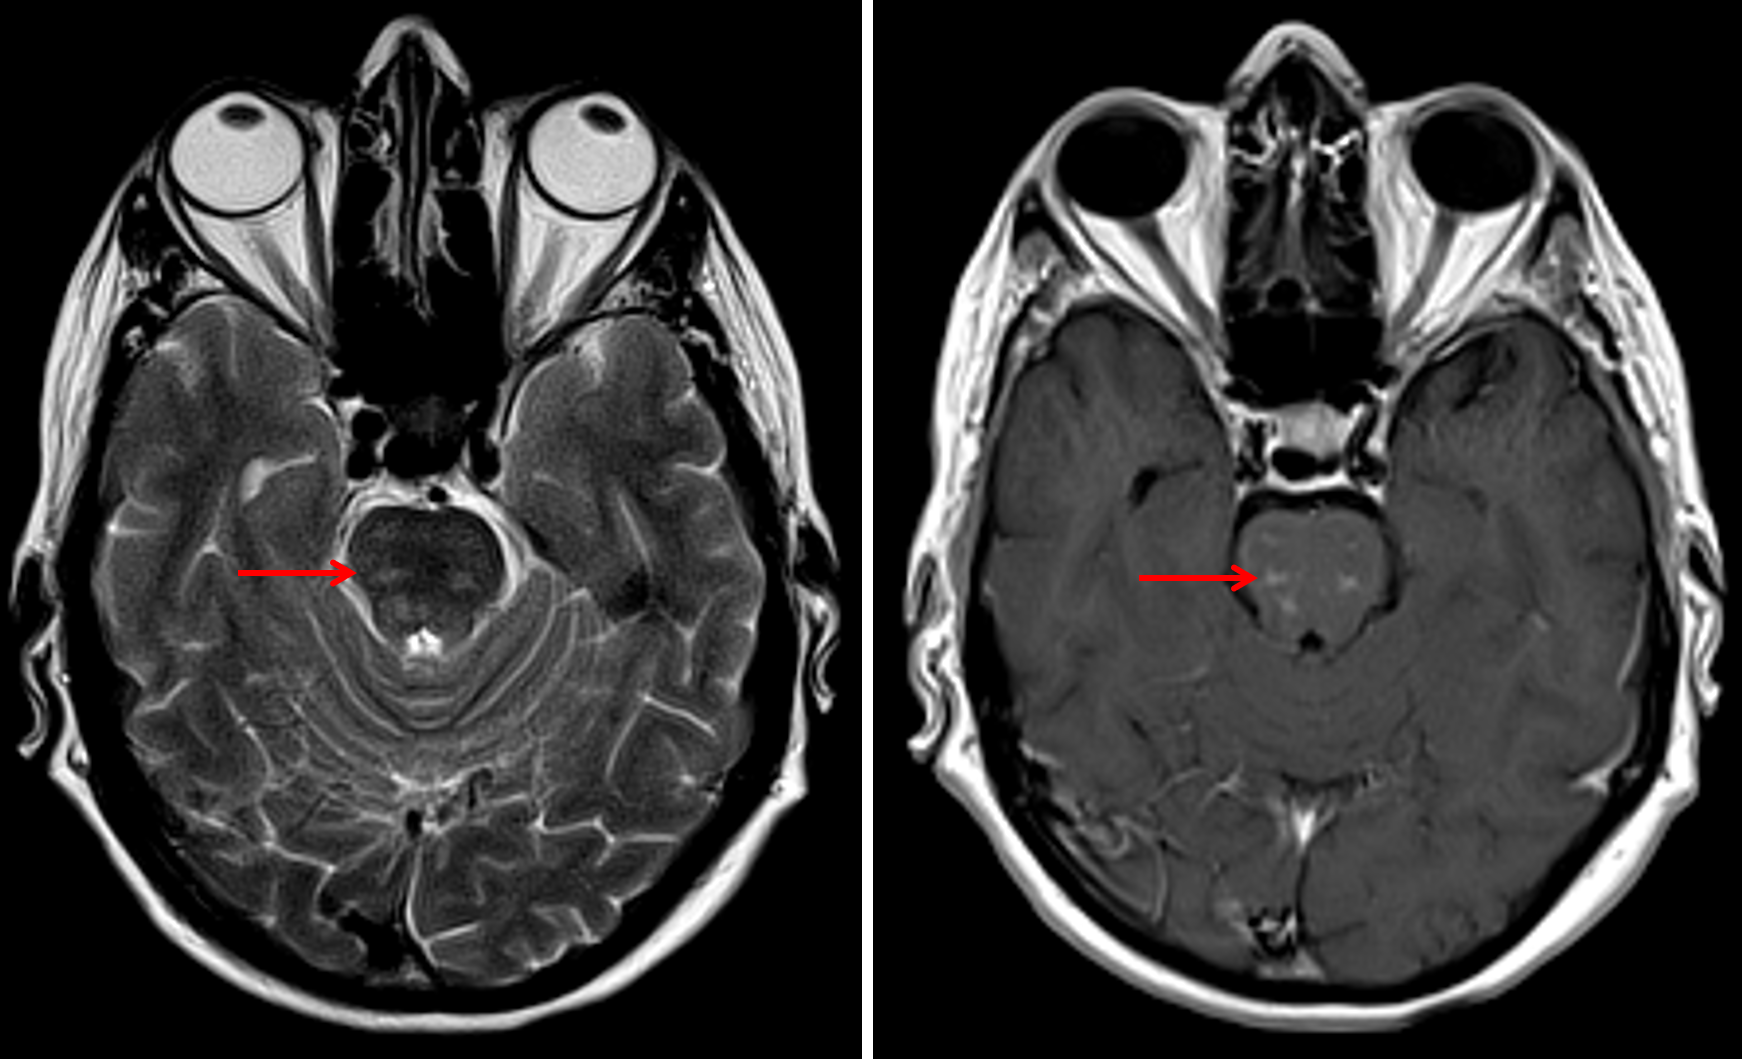

Age: 67

Sex: Female

Indication: Ataxia

Chronic lymphocytic inflammation with pontine perivascular enhancement responsive to steroids (CLIPPERS)